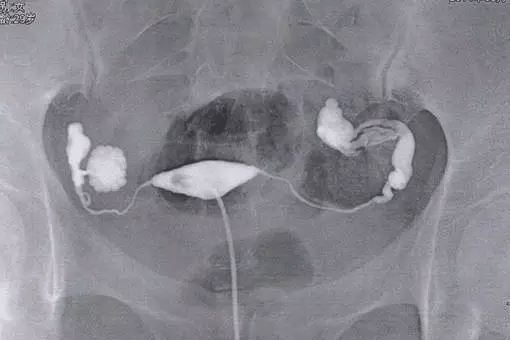

子宫输卵管造影是判断输卵管疏通与否的一种检查方法,包括输卵管造影在内,关于输卵管检查的几种类型还有输卵管通液、超声检查、腹腔镜检查、输卵管通气试验等,以上这些都是针对女性输卵管是否正常的一些检查方法。

由于输卵管造影副作用小、对患者造成的不适感弱,因此子宫输卵管造影术在临床应用中相对广泛,一般使用该方法进行检查的最佳时间为月经干净后3~7天内,患者在术前需严格按照医生嘱咐进行准备。

输卵管造影术检查过程

整个输卵管造影流程下来,对女性身体的伤害较小,同时在有经验的医验操作下准确率高达98%,输卵管造影相比宫腔镜、腹腔镜、输卵管镜等检查来说,在许多方面是无法替代的,下面来看看详细的输卵管造影过程:

①、在进行输卵管造影检查时,首先患者需要仰卧在X光机操作平台上,先常规消毒外阴及阴道,同时铺无菌巾,再次检查子宫位置及大小;

②、随后在医生会用窥器扩张阴道,暴露宫颈,消毒完毕后再将宫颈管顺着宫腔的方向插入,然后在拉紧子宫颈钳使导管之锥形橡皮头与宫颈紧紧相贴,以防止药物的流出;

③、然后只需要在X线透视下观察造影剂流经宫腔,再慢慢注入碘油,观察子宫及流经输卵管的情况,此时会拍摄一张照片然后会继续推入碘油,5--10分钟后继续拍片;

④、间隔一天时间后会在同部位拍摄,如果双侧输卵管不通那么久不会有游离的碘海醇,如果有少量碘海醇那么确定为输卵管通而不畅。